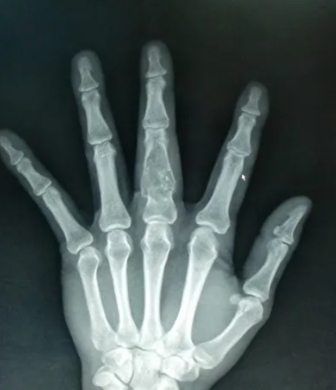

找到这些影像征象,复杂的骨肿瘤迎刃而解

骨肿瘤的基本影像学征象是构成骨肿瘤最基本的元素,无论多复杂的骨肿瘤都由一个或几个基本影像学征象构成,对其透彻理解和准确把握是正确诊断骨肿瘤的重要前提。